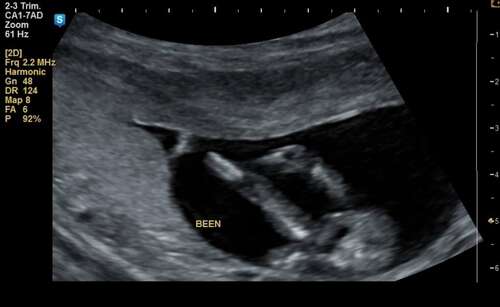

Wat maken jullie hiervan? 💗💙

Dit is nog te vroeg